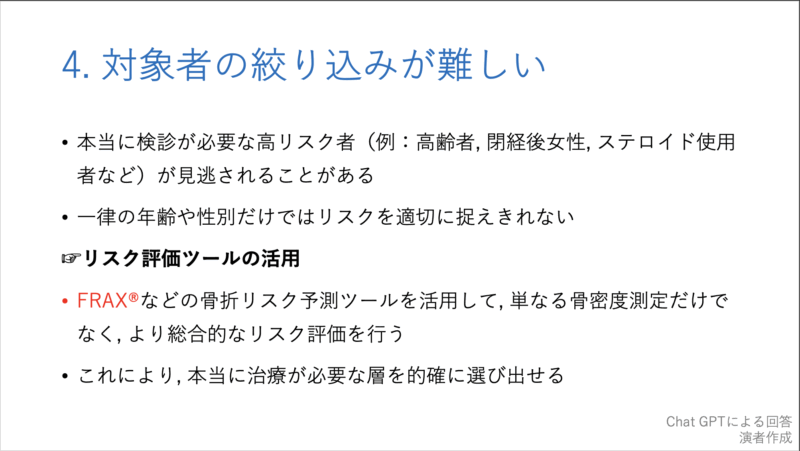

20時過ぎから, 私がclosing remarksとして, 10分で骨粗鬆症検診の問題点とその対策, および各県庁所在地での現状について, チャットGPTからの回答をからめてお話ししました. 途中で, 自分の大腿骨頚部骨折のことも取り上げました.